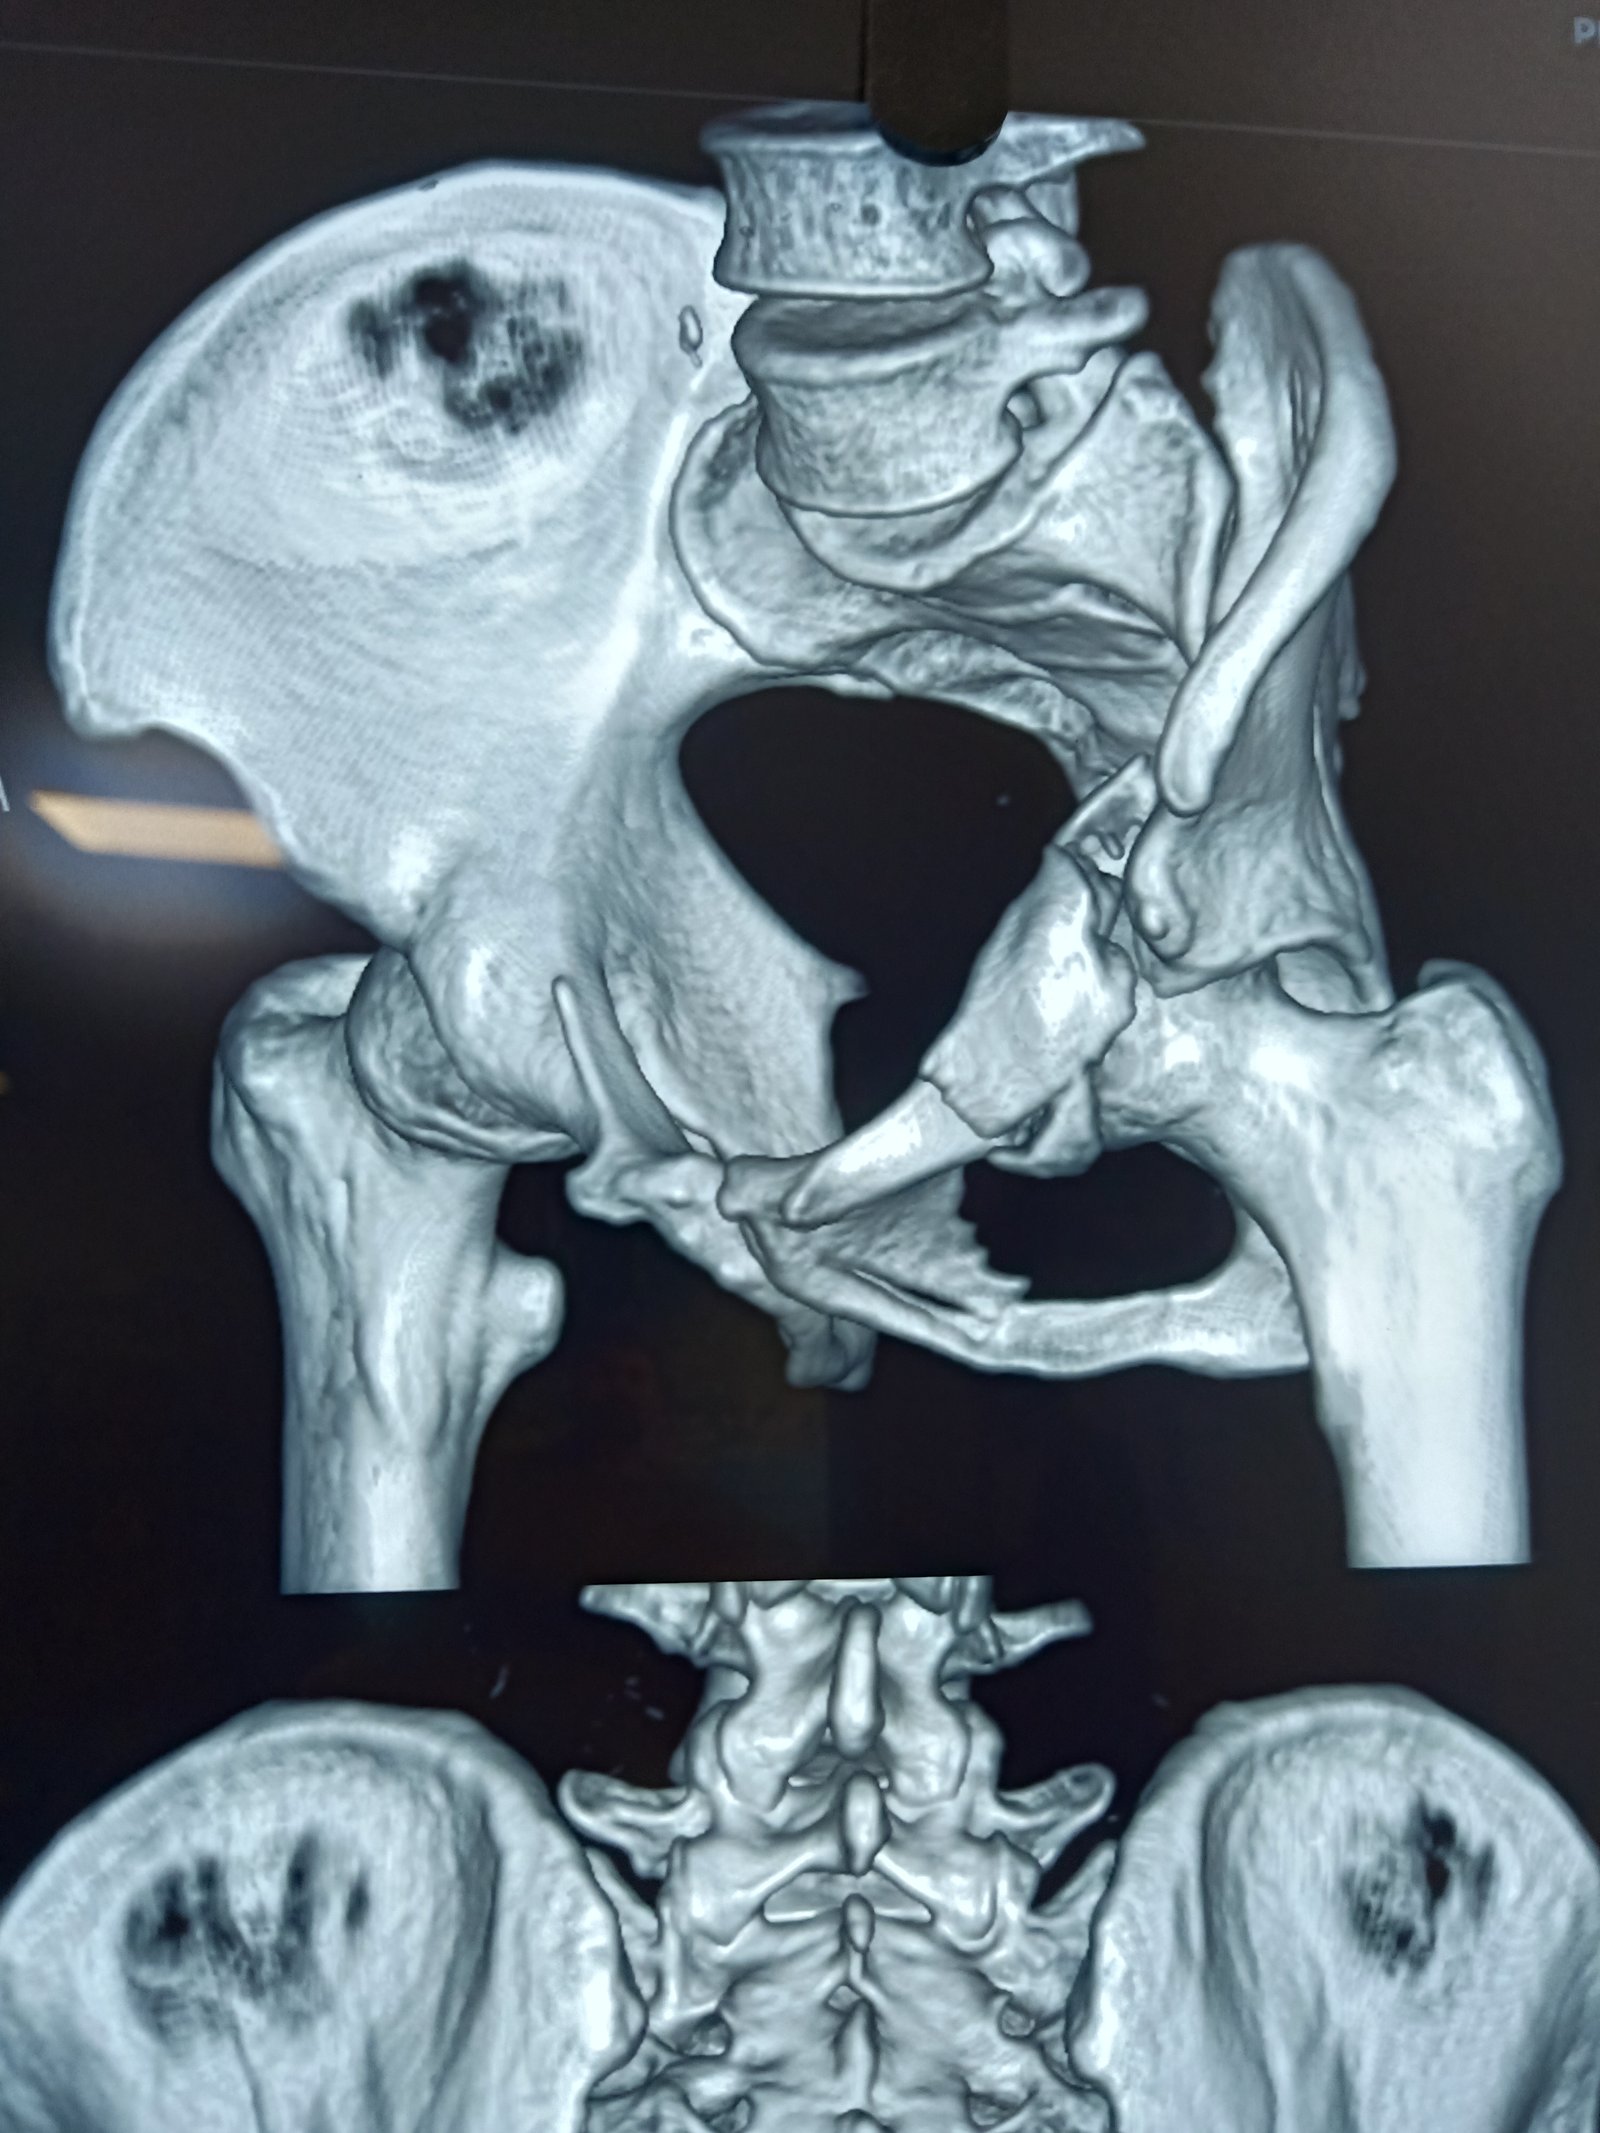

acetabulum

anterior collumn of acetabulum fixation done via anetrior appoach